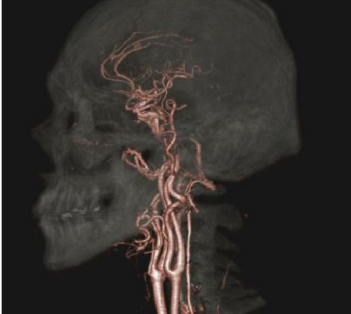

(3)應用 Intelli IP(Advanced)進行高質量的叠代重建

Intell IP(Advanced)是針對低劑量圖像重建算法中的創新,其有效性在以往的用戶中得到了證明。